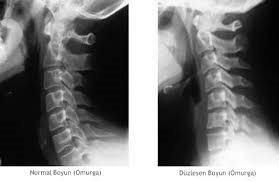

Boyun Düzleşmesi nedir?

Servikal lordoz, servikal omurganın içe doğru eğrilmesini ifade eder. Bu eğrilik, baş ve boynun omuzlar üzerinde dengelenmesine yardımcı olarak ağırlık ve stresin optimum dağılımını sağladığı için hayati önem taşır.

Hipolordoz ve Hiperlordoz

Boyun eğriliğinin azalması (hipo-lordoz) veya fazla artması(hiper-lordoz) sorunlarına yol açabilir. Boyundaki bu değişiklikler kötü duruş, omurga yaralanmaları veya doğuştan omurga rahatsızlıkları gibi faktörlerden kaynaklanabilir.

Servikal Lordoz Kaybının Belirtileri

Servikal lordoz, servikal omurganın (boyun bölgesi) doğal ve doğru açıdaki içe doğru eğriliğini ifade eder. Bu eğri azaldığında “servikal lordoz kaybı” veya ” düzleşmesi” olarak adlandırılır. Bu omurga hizalanmasındaki değişiklik, kötü duruş, kas zorlanması, travma, doğuştan anomaliler, dejeneratif değişiklikler veya diğer omurga rahatsızlıkları gibi çeşitli nedenlerden kaynaklanabilir.